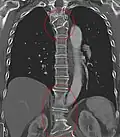

Block vertebrae

Block vertebrae occur when there is improper segmentation of the vertebrae, leading to parts of or the entire vertebrae being fused. The adjacent vertebrae fuse through their intervertebral discs and also through other intervertebral joints so that it can lead to blocking or stretching of the exiting nerve roots from that segment. It may lead to certain neurological problems depending on the severity of the block. It can increase stress on the inferior and the superior intervertebral joints. It can lead to an abnormal angle in the spine, there are certain syndromes associated with block vertebrae; for example, Klippel–Feil syndrome. The sacrum is a normal block vertebra.[8]